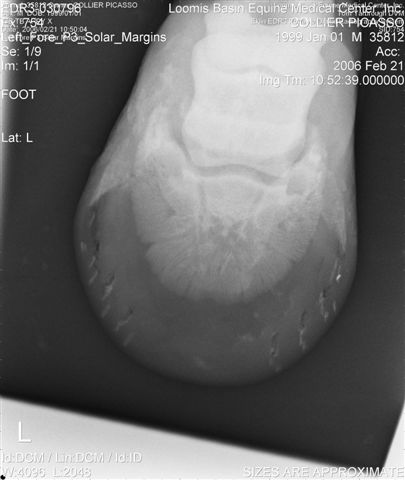

Let's label the radiographs from left to right with numbers. The abnormalities I see on the L using the photo's number as reference:

1) Odd lucency (darker) at the top/lateral margin of the coffin bone (seen in many images). It would interesting if this is also the site of the odd bruising.

2) Decrease lucency (darker) in the body of the navicular bone.

2) Remarkable cone shape areas of decrease lucency (darker) along the distal margin of the navicular bone.

3) Assymetrical flexor surface of the navicular bone.

4) There is the appearance of poor ap balance of the foot with the heels being low

4) Soles appear thin

4) Small osteophyte (bone spur) on the front margin of the pastern joint.

Unless there is something I am missing in the images the extensor process appears to have healed well on the L. The significance of each of these lesions will depend on clinical findings Ann and confirmation that these are actual lesions and not artifacts created by positioning or the foot preparation for radiography. You should note I am not a radiologist and that viewing images in this manner is not as revealing as viewing the radiographs first hand.